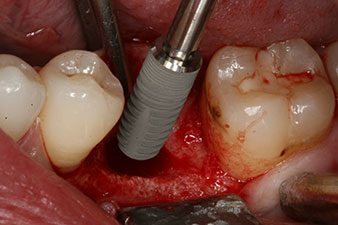

Sechs Wochen nach Extraktion zeigte sich jedoch nach Präparation des Mukoperiostlappens im Bereich der ehemaligen mesialen Alveole eine unvollständige Ossifikation.

Nach gründlicher Entfernung des Granulationsgewebes wurde das Implantat wie geplant eingebracht (blueSky, bredent).

Das Drehmoment beim maschinellen Einbringen war 43 Ncm. Zusätzlich wurde, nach Einschrauben eines speziellen, auf das Implantatsystem abgestimmten Mess-Pfostens (SmartPeg), der ISQ-Wert mit der Sonde des W&H Osstell ISQ Modul bestimmt.

Dieses Modul ist für das Implantmed von W&H optional erhältlich und wird an den Implantologiemotor gedockt (vgl. Abb. 11). Der dimensionslose ISQ-Wert war direkt bei der Insertion 64 in oro-vestibulärer und 68 in mesio-distaler Richtung (Maximalwert = 100). Dies hätte eine offene Einheilung oder sogar Sofortversorgung erlaubt.

Wegen des unzureichenden Knochens krestal am Implantat wurde der Bereich mit den bei der Präparation des Implantatlagers gesammelten Knochenspänen augmentiert und speicheldicht vernäht.